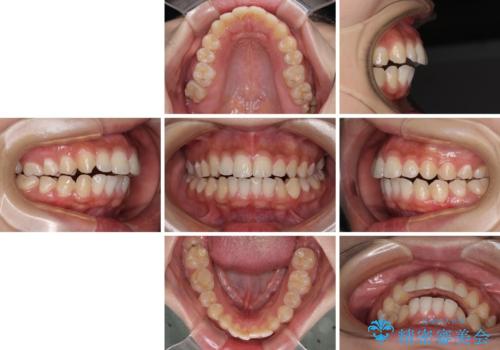

前に出ている上顎 抜歯矯正で唇を閉じやすく

- 口元の突出感と上下前歯のズレを気にして来院された患者様です。

舌の突出癖により上下の前歯は非接触であり、更には奥歯の咬み合わせが非対称となっている状態でした。

通常は上下左右の第一小臼歯4本を抜歯することになりますが、右側臼歯部の咬合が上顎前突気味であったため、下顎右側のみ第二小臼歯を抜歯し、ワイヤー装置にて矯正治療を行うこととしました。